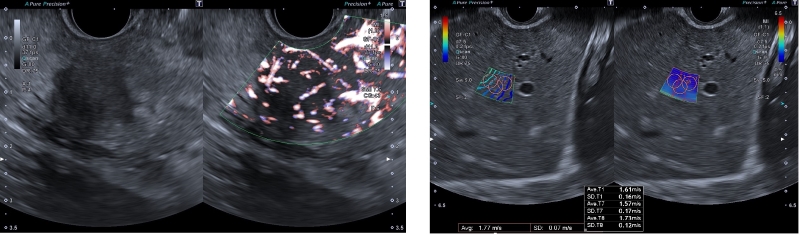

A wide variety of EUS-supporting functions are provided to support reliable diagnosis and treatment decisions. SMI (Superb Micro-vascular Imaging), Canon Medical's proprietary technology, is a blood flow imaging technique that captures minute and slow blood flow. It supports safer procedures, even when performing puncture under ultrasound control, because it can depict low-velocity blood flow with high sensitivity, high resolution, high frame rate1, and low artifacts2, which may be difficult to depict with color Doppler3.4 “SMI allows detailed visualization of microvascular structures. With SMI, I feel more confident in my procedures.” says Dr. Khanh Do-Cong Pham from the Haukeland University Hospital in Bergen, Norway. SWE (Shear Wave Elastography) is a technology that displays tissue hardness as a numerical value or color map, enabling a more objective evaluation of hardness.

Left: SMI / Right: SWE